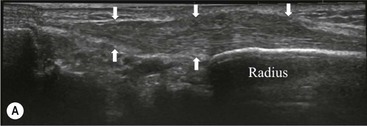

The affected tendon is thickened and hyporeflective on US, with neovascularisation on Doppler imaging (Fig. 46-16). High SI is demonstrated on fluid-sensitive MRI sequences (Fig. 46-17). Tendon tears are demonstrated as focal areas of deficiency.13 In chronic cases, new bone formation may be seen on radiographs at the tendon enthesis. Calcific tendinopathy is much less common than in the rotator cuff of the shoulder.